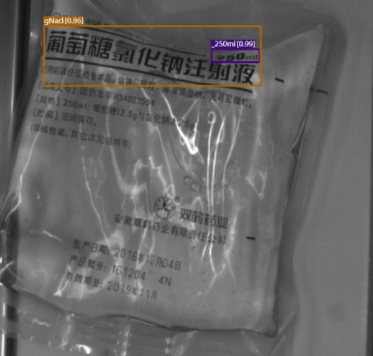

AI-Powered Feature Recognition

With SolVision‘s segmentation tool, various labels can be identified from sample images to train a visual inspection system capable of classifying information on IV bags based on their distinctive features. SolVision’s advanced AI-based technology is also unaffected by transparent objects, label complexity, or appearance.